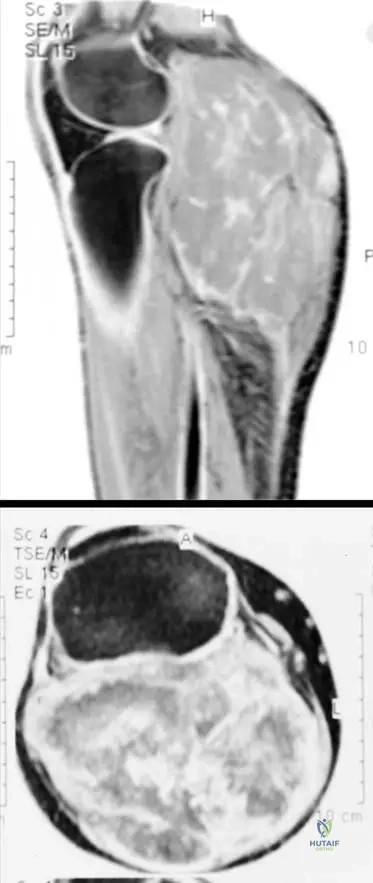

Correct Answer: A

Rationale: The clinical context for Fig. 9.19 states: "Axial T1(a) and axial T2-weighted MRI with fat saturation (b) showing typical MRI features of a soft tissue sarcoma with intermediate signal intensity on T1 (isointense with muscle)." Main Distractor: B) Markedly high signal intensity, brighter than fat. This is incorrect; T1 signal for STS is typically intermediate, isointense with muscle, not markedly high like fat.

Rationale: The clinical context for Fig. 9.19 states: "Axial T1(a) and axial T2-weighted MRI with fat saturation (b) showing typical MRI features of a soft tissue sarcoma with intermediate signal intensity on T1 (isointense with muscle) and markedly heterogeneous predominantly high signal intensity on T2." Main Distractor: B) Homogeneous low signal intensity. This is incorrect; sarcomas typically show high signal on T2, and often with heterogeneity, not homogeneous low signal.

Rationale: The clinical context for Fig. 9.19 states: "Note that the tumor originates within the deep muscular compartment of the thigh." Main Distractor: B) Subcutaneous compartment. While some sarcomas are subcutaneous, the text specifically states this particular tumor (Fig 9.19) originates in the "deep muscular compartment."